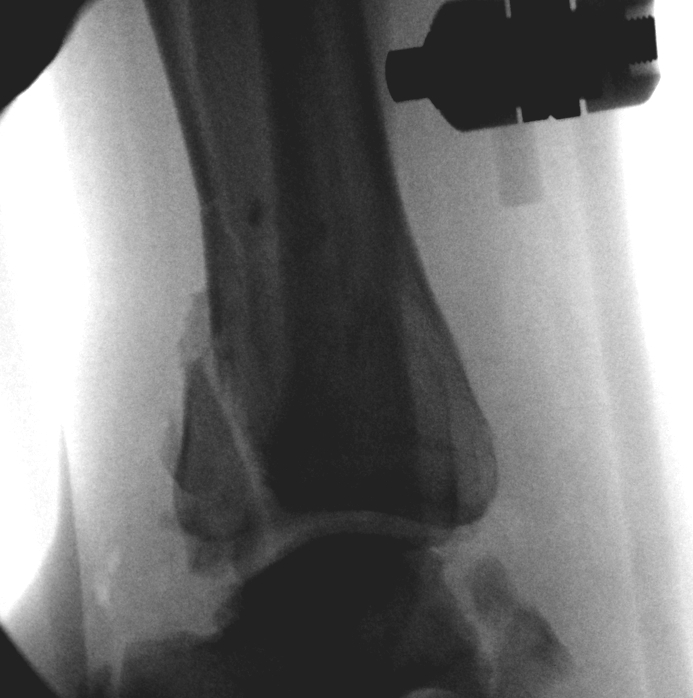

Staged treatment - External Fixation followed by delayed fixation

Spanning external fixation

- holds out length

- helps soft tissues recover

- wait until swelling down

- wrinkled skin, blisters resolved

- wait 3 weeks plus if needed

Technique of ankle bridging delta frame

- two pins in the tibia away from surgical site

- transcalcaneal threaded pin placed medial to lateral

- pin in base of first metatarsal to keep foot in neutral position and prevent equinus contracture

- note: pin in base of first metatarsal places deep plantar branch of dorsalis pedis at risk

Tibial Plafond Pre External Fixator APTibial Plafond Pre External Fixator LateralTibial Plafond Post External Fixator APTibial Plafond Post External Fixator Lateral